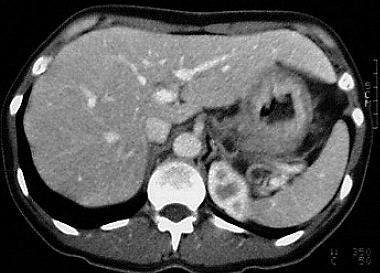

the pathological image-left and the physiological image-right

Thickening

of the wall

of the whole stomach.

D:

Carcinoma of

the stomach (linitis plastica)